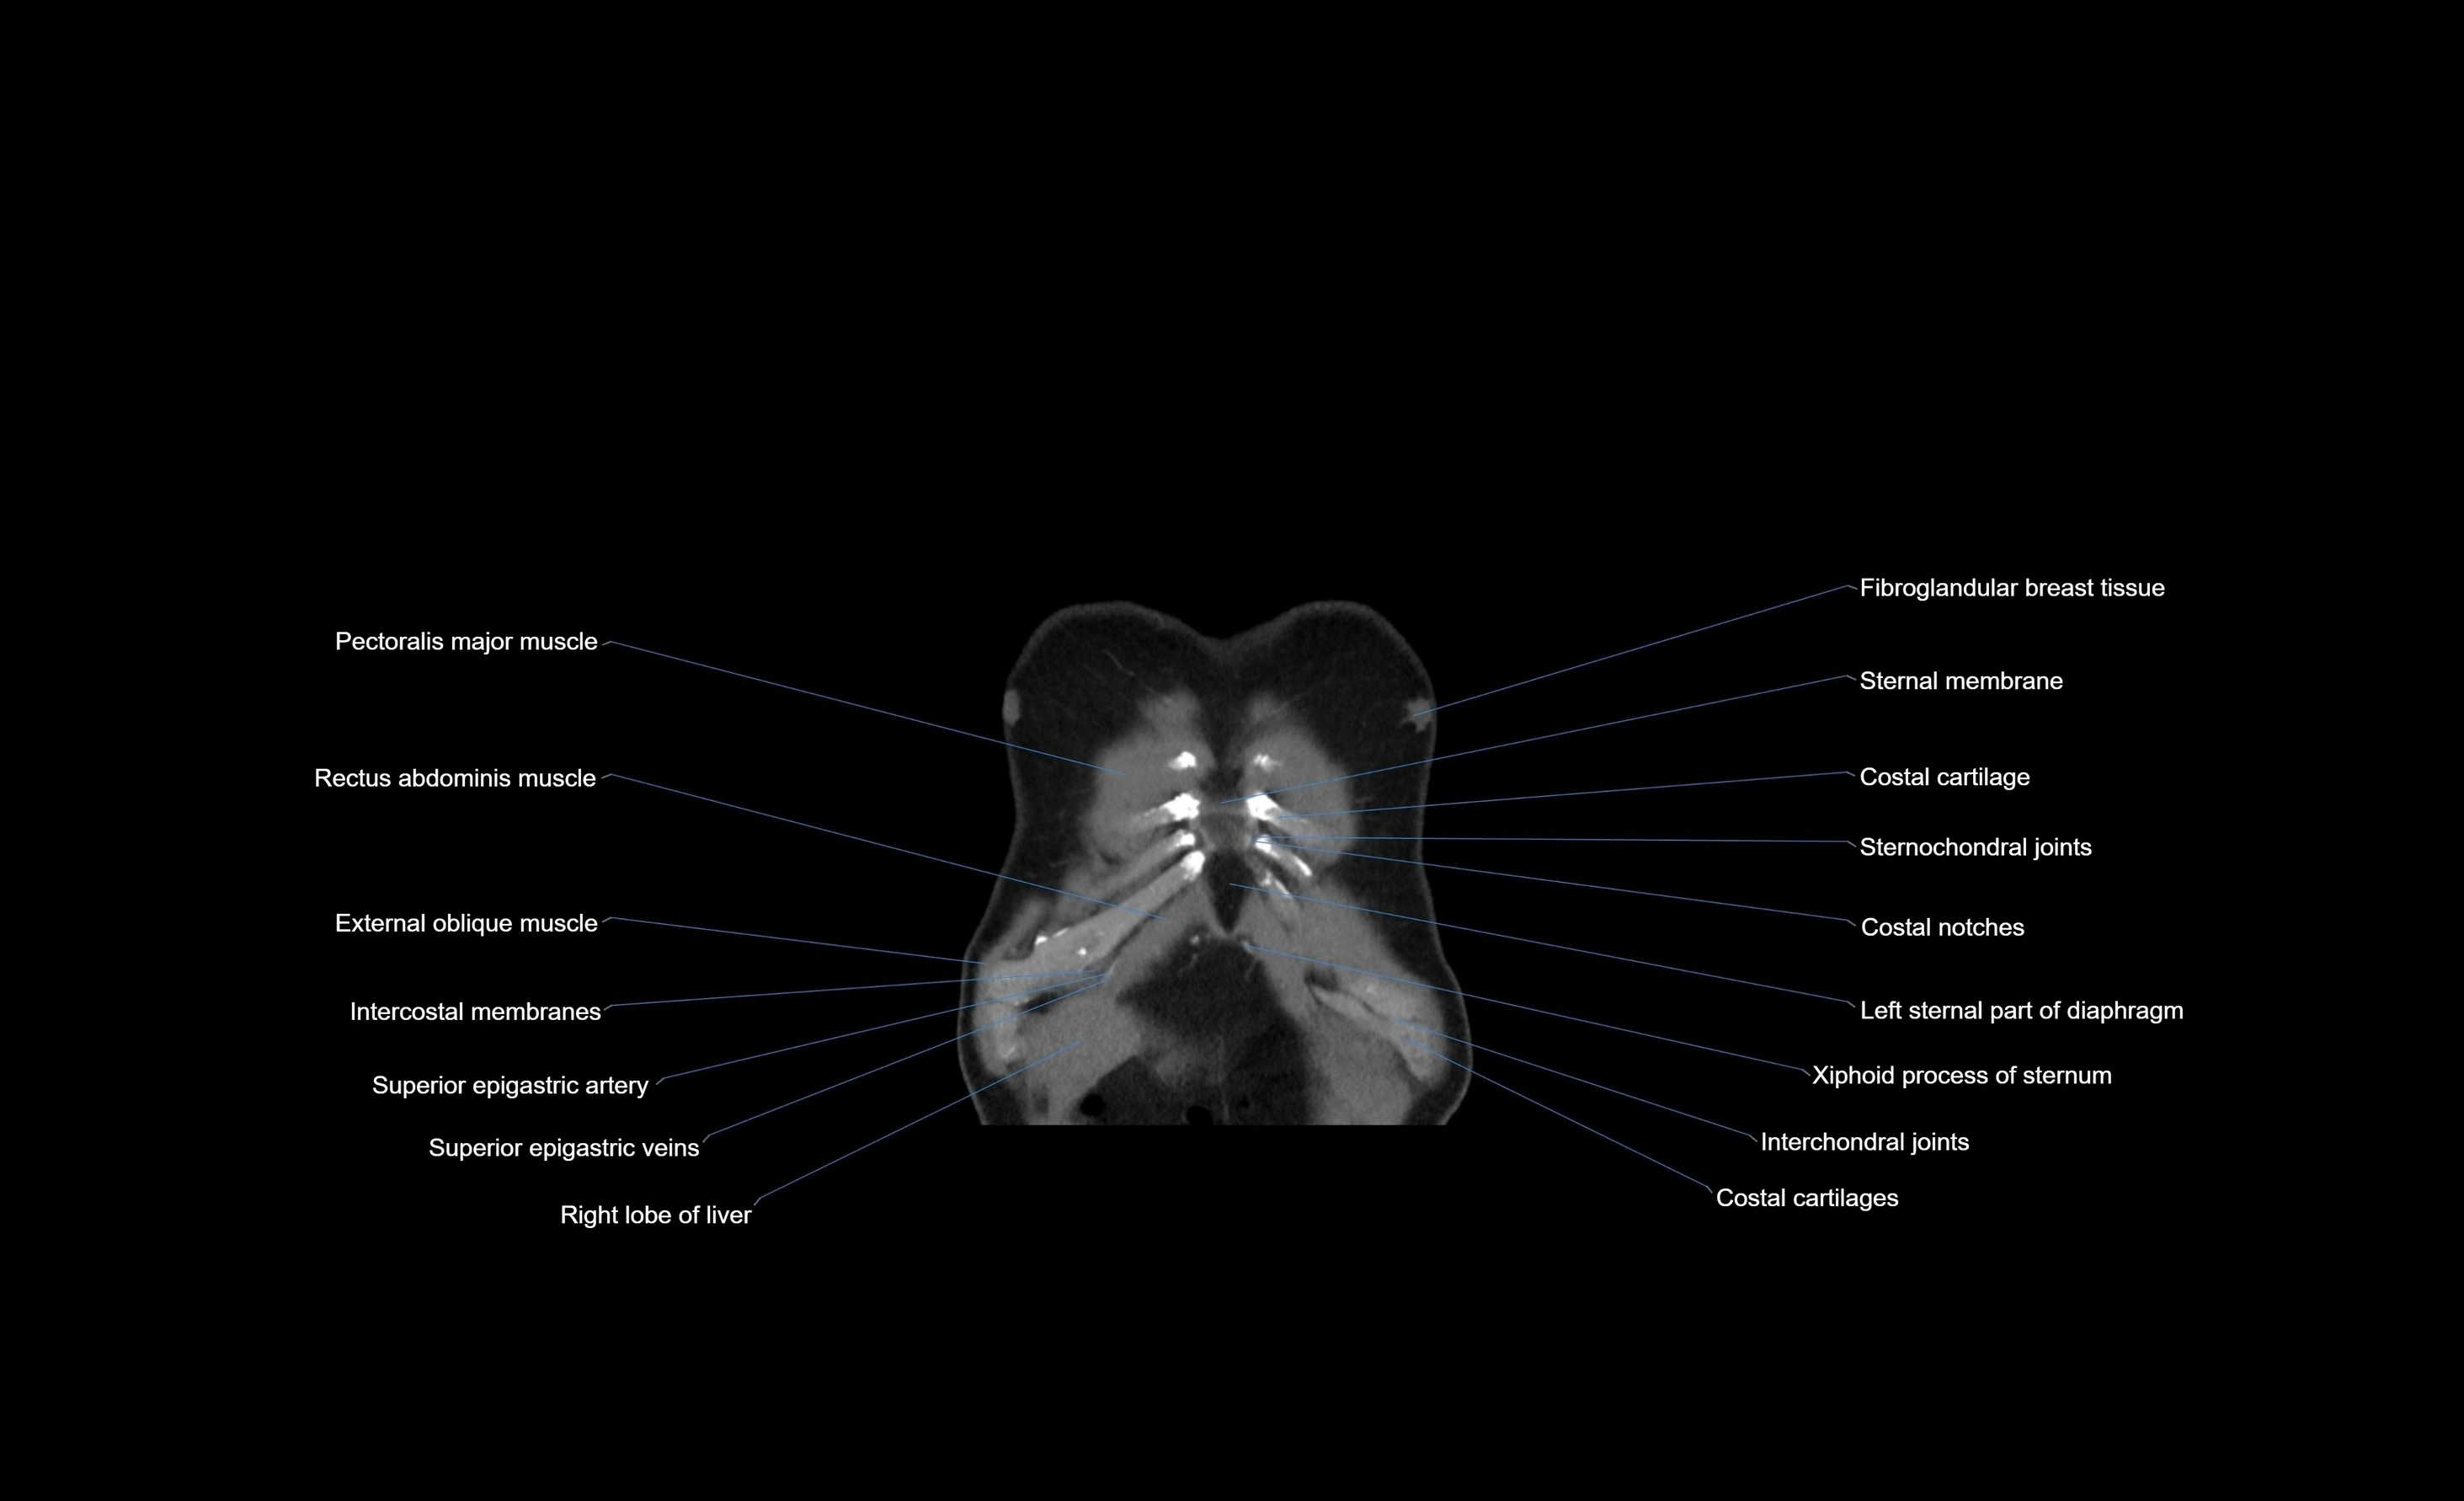

- Pectoralis major muscle

- Rectus abdominis muscle

- External oblique muscle

- Intercostal muscles

- Superior epigastric artery

- Superior epigastric veins

- Right lobe of liver

- Costal notches

- Sternal part of diaphragm

- Costochondral joints

- Xiphoid process of sternum

- Costal cartilages